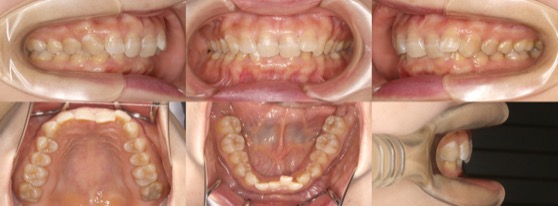

為您介紹隱適美矯正的治療案例。

※案例圖片著作權:隱適美醫師網(禁止轉載)

從案例照片的矯正前後對比中,可以清楚地看出其效果。